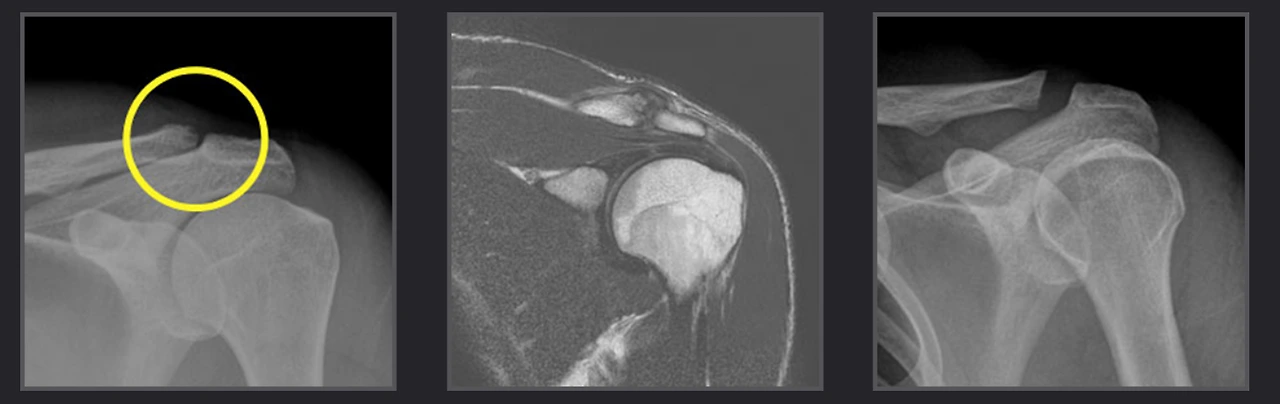

견봉관절염.PNG

X-ray에서 쇄골에 골 침식이 보이며 관절내시경으로는 관절 연골의 손상과 활막에 염증이 생긴 것이 보이는 상태입니다. “이런 경우에는 관절내신경으로 쇄골의 침식된 끝부분을 절제하고 염증조직을 제거하는 수술을 하게 되지요”라고 기세린 원장님은 설명하며 10만 명 이상의 풍부한 임상경험을 가지고 있는 어깨 스포츠 메이저 대학병원 전임의 출신 의료진이 진료하는 에이스병원에서는 환자의 골격 모양과 관절염의 정도에 따른 다양한 시스템의 인공관절 수술이 진행된다고 알려주십니다.

인공관절치환술.PNG

팔을 들지 못하는 가성마비를 보이는 복원이 불가능한 광범위 회전근개파열환자에서 관절염이 진행한 경우에 주로 사용하는 수술법입니다. 손상된 어깨 관절을 인공관절로 대체하는 어깨 인공관절치환술 후 운동범위가 향상되고 동통의 완화 및 기능 향상으로 일상생활이 편해집니다.